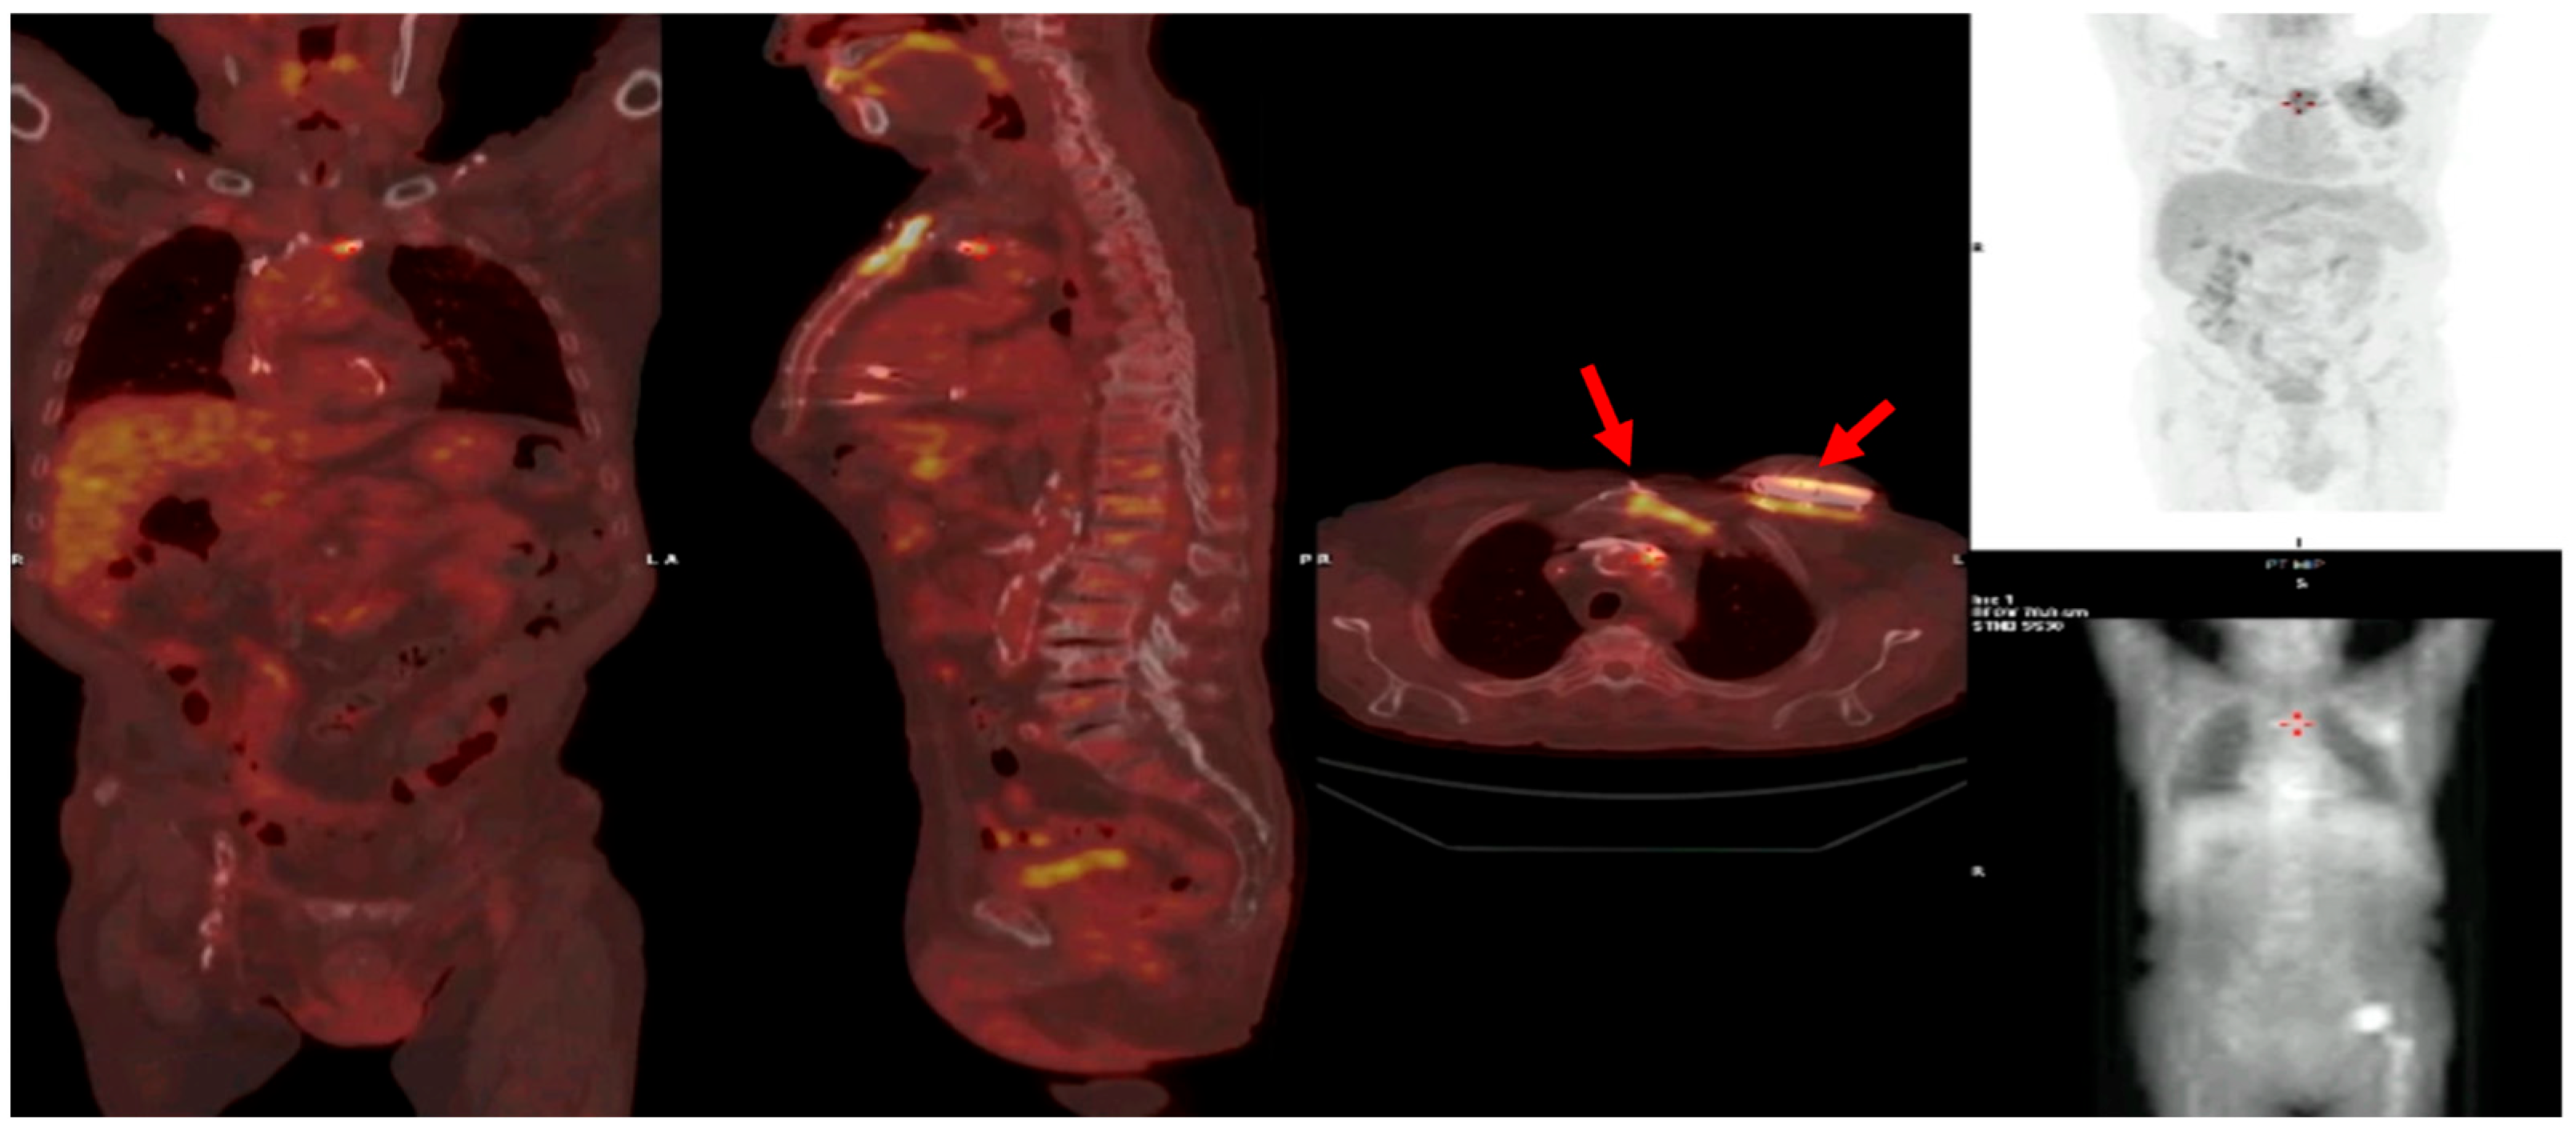

- Prosthetic valve endocarditis (PVE): FDG-PET/CT and WBC scintigraphy are recommended when echocardiography is inconclusive or negative, but clinical suspicion remains high. These modalities are especially valuable for detecting perivalvular infection, invasive complications, and extracardiac septic emboli. Abnormal focal uptake around the prosthesis is considered a significant criterion for PVE diagnosis, and can reclassify cases from “possible” to “definite” IE within the modified Duke criteria framework [13,43,44,45]

- Cardiac device infections: Nuclear imaging is indicated for suspected infection of cardiac implantable electronic devices (CIEDs) when conventional imaging is non-diagnostic. FDG-PET/CT can identify device pocket infection, lead infection, and associated extracardiac complications, and is integrated into the diagnostic algorithm for device-related IE [46]

- Reclassification from possible to definite IE: The ESC guidelines incorporate abnormal FDG-PET/CT or WBC scintigraphy findings as a significant criterion for IE diagnosis in patients with prosthetic valves or devices. This allows for reclassification of cases initially deemed “possible” IE to “definite” IE when nuclear imaging demonstrates focal uptake consistent with infection, particularly in the setting of non-diagnostic echocardiography or ambiguous clinical findings (Figure 16, Figure 17 and Figure 18) [43,44,46].